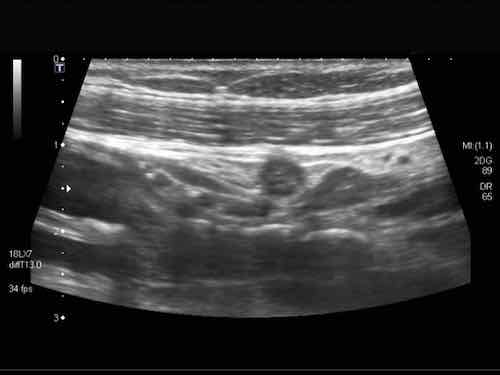

Intussusception

Đây là hình ảnh siêu âm của một trẻ 2 tuổi bị lồng ruột hồi manh tràng từng đợt, được khám trong khoảng thời gian giữa các cơn.

Hồi tràng với nhiều mảng Peyer sa vào manh tràng.

Hình ảnh siêu âm kinh điển của lồng ruột hồi-manh tràng ở hai trẻ khác nhau.

Trong cả hai trường hợp, đoạn hồi tràng bị lồng được định vị không đối xứng bên trong ống lồng ngoài, do mạc treo ruột tăng âm có chứa mỡ, bám vào hồi tràng và đi theo hồi tràng khi bị kéo vào trong.

Trong mạc treo, siêu âm cho thấy một hạch bạch huyết mạc treo (hbh) phóng đại ở cả hai.

Các hạch này phì đại như một phần của tình trạng tăng sản hạch bạch huyết toàn thân và khônghu trú trong lòng hồi tràng.

Do đó đây không phải là điểm dẫn đầu nguyên phát. Ở bệnh nhân bên phải, ruột thừa (mũi tên) cũng bị kéo vào trong.

Lưu ý cấu trúc đa lớp của thành bụng phía trước của phức hợp lồng ruột, đại diện cho ba lớp thành ruột bị gấp lại.